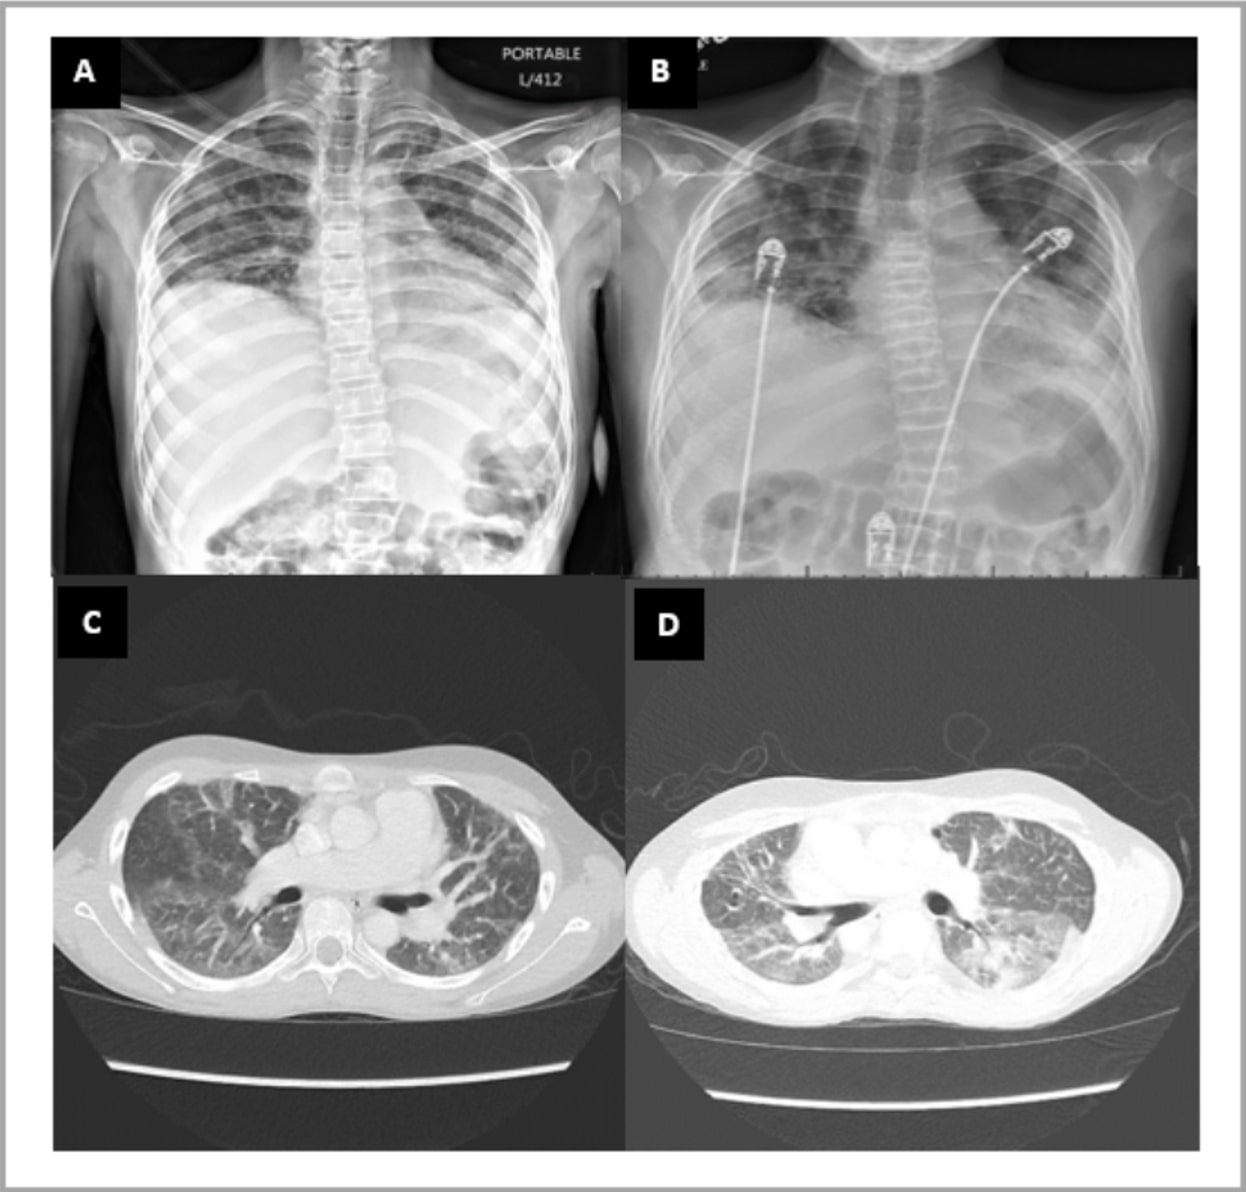

Figure 1 (A-D). Radiologic findings in a patient with Jo-1 Interstitial Lung Disease

Chest radiograph (A and B) and CT Chest without contrast (C and D). Images show low lung volumes, multifocal bilateral ground glass opacities, more pronounced at the lung bases. Findings supportive of nonspecific interstitial pneumonia. Note the architectural distortion/fibrosis throughout both lungs and bone demineralization with multilevel vertebral body compression fractures developed over time.